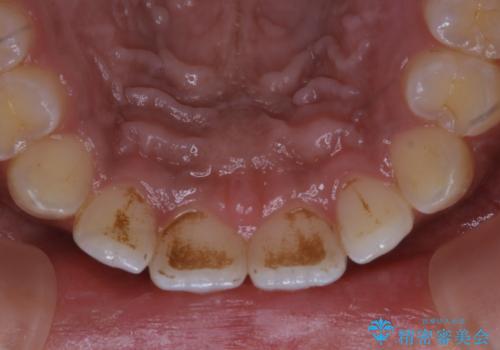

タバコのステインを徹底的に除去

- タバコによるステインを綺麗にしたいとのことでした。

タバコに含まれているものの中で、タールというものが歯の黄ばみの原因です。その黄ばみなどを、無理に落とそうとしたりすると歯の表面に傷がついてしまったり余計に汚れがつきやすい状態になることがあります。